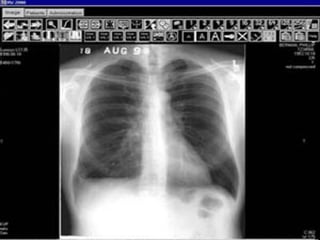

RAIOS-X DIGITAL

Com  o  avanço  tecnológico  informática

levou  a  uma  tendência  para  a  gerações

de  imagens  digitais,  e  os  exames

tradicionais de raios X a ser adquiridos e

processados  pelo  computador.  A

aquisição e análise de imagens digitais

de raios X  formam  a  base  do  campo

chamado radiologia digital.